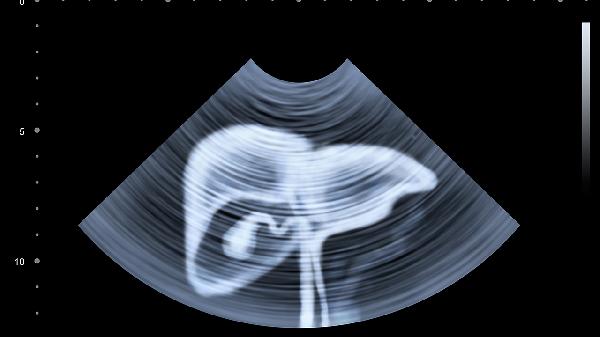

肝脏的求.救信号往往伪装成普通小毛病,建议有乙肝、长期饮酒、脂肪肝病史的人群,每半年做一次腹部B超和甲胎蛋白检查。40岁以上人士体检时建议加做肝脏弹性检测。记住,肝脏疾病进展是个缓慢过程,每次身体发出异常信号,都是它给你的自救机会。